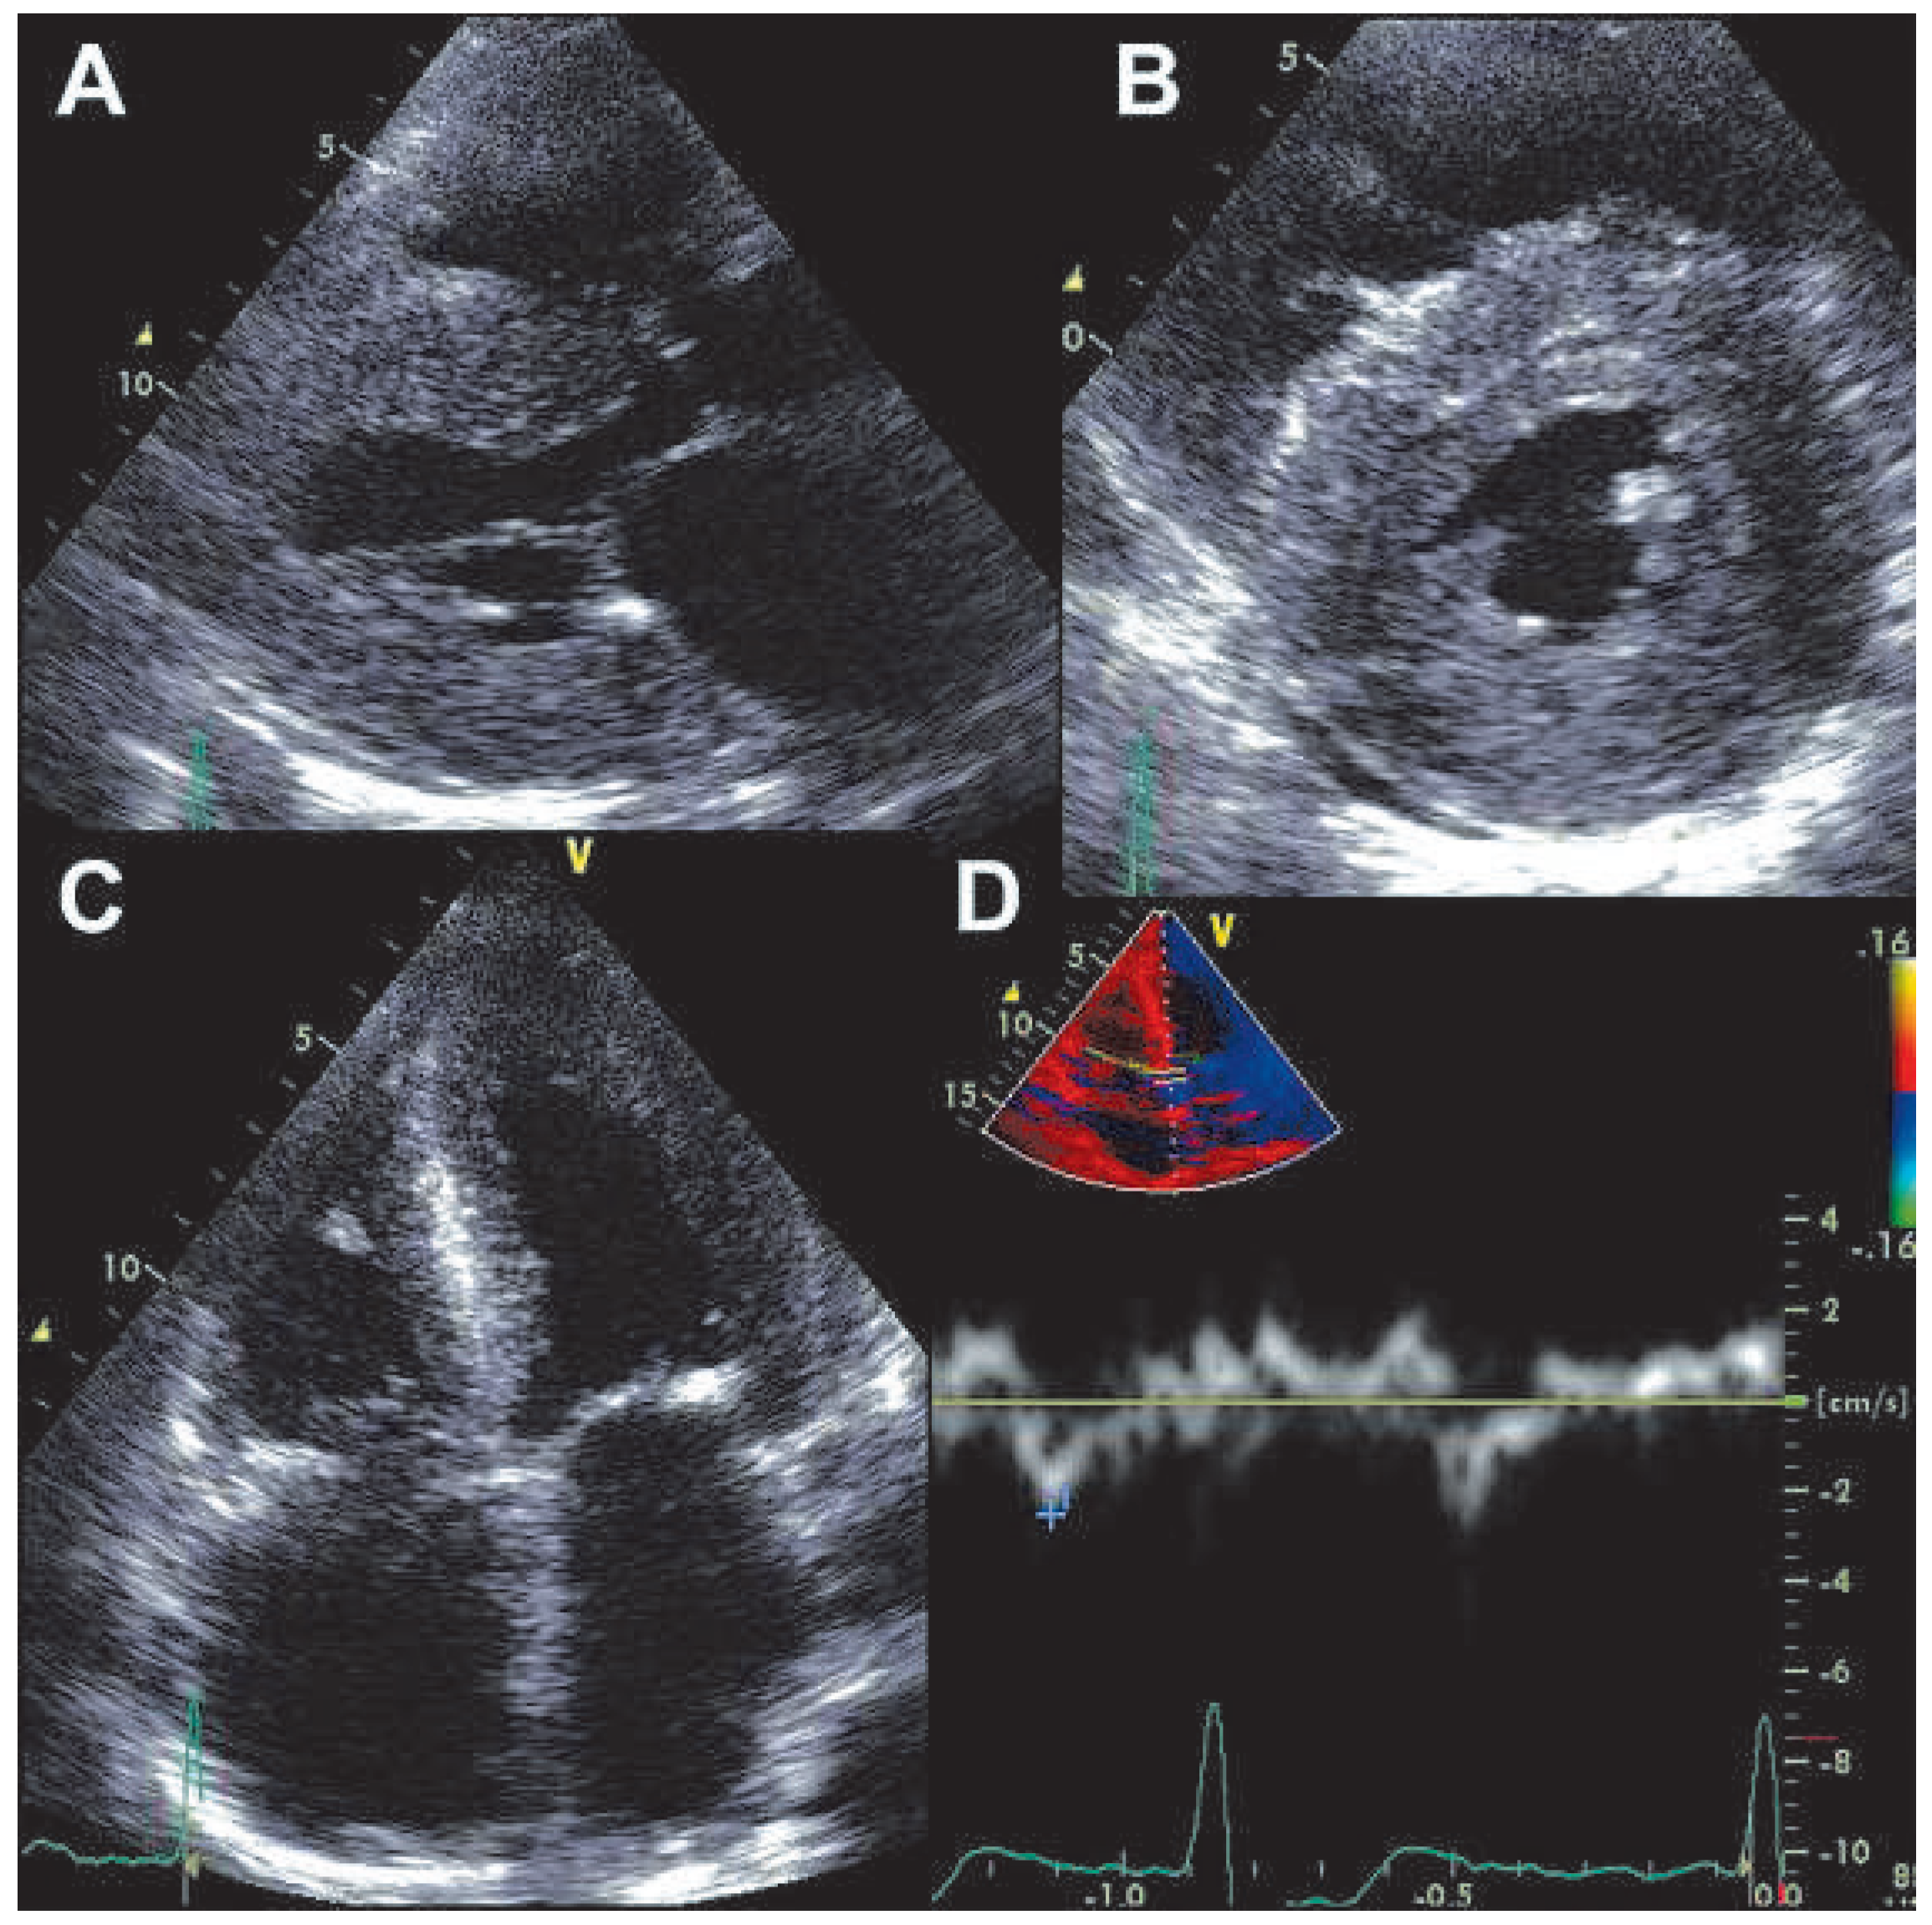

A 66-year-old woman was referred because of suspected acute coronary syndrome (ACS). On admission the patient was complaining of chest pain irradiating into her back, and she also had shortness of breath on minimal exertion and even at rest. Blood pressure was 134/89 mm Hg, pulse was regular (82 bpm). Physical examination revealed evidence of biventricular cardiac decompensation with lower leg edema, congested neck veins, and bibasilar crackles. Chest X-ray confirmed pulmonary venous hypertension. The ECG showed sinus rhythm and extensive pathological Q waves in leads II, III, and aVF as well as the praecordial leads V1–V4 (Figure 1). Plasma concentration of B-type natriuretic peptide was 3287 ng/l (normal <50 ng/l), and cardiac troponin I was mildly elevated (1.92 µg/l, normal <0.5 µg/l). There was evidence of renal failure (estimated glomerular filtration rate 35 ml/min/1.73 m2). The bedside echocardiogram (Figure 2) performed for triage of ACS revealed a normal-sized left ventricle with symmetrically and massively increased wall thickness (left ventricular end-diastolic diameter 43 mm, interventricular septum 28 mm, posterior wall 23 mm) with a speckled appearance of the myocardium, diffusely impaired contractility (left ventricular ejection fraction 35–40%, long axis shortening virtually absent, radial shortening preserved), a restrictive mitral inflow pattern with significantly reduced tissue velocities (peak early diastolic mitral annular velocity [e’] measured at the septal annulus 3 cm/s), biatrial dilatation, and a small pericardial effusion. Ultimately a diagnosis of AL-amyloidosis was obtained based on amyloid deposits in the abdominal fat pad fine needle aspirate and free light chains in serum. Bone marrow biopsy did not show evidence of multiple myeloma. Chemotherapy with alkeran, dexamethason, and thalidomide was initiated but the patient died six weeks after the initial presentation.

Figure 2. Transthoracic echocardiogram. Panel A: parasternal long-axis view showing symmetrically increased left ventricular wall thickness and left atrial dilation. Panel B: parasternal short axis view showing symmetrically increased left ventricular wall thickness with concentric left ventricular geometry and small pericardial effusion. Panel C: apical four chamber view showing symmetrically increased left ventricular wall thickness and biatrial dilatation. Panel D: pulsed wave tissue Doppler recording at the septal mitral annulus showing significantly reduced peak early mitral annular velocity.